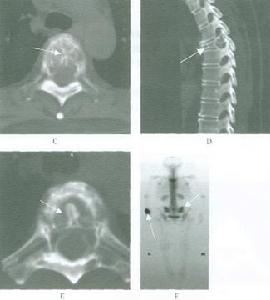

有經驗的骨腫瘤醫生僅憑X線平片就可以作出骨囊腫的臨床診斷。病變灶為邊界清晰的液性低密度灶,四壁為薄層的硬化灶殼。病變灶略向近骨骺的乾骺部位擴大。病灶非偏心性,也不破壞骨外殼,更不會突破骨質形成骨膜外反應骨,除非是在病理骨折後的癒合期。有時脫落的骨皮質成份落入囊腔中,X片顯示被稱為“落葉征”(FallenleaforFallenfragment)。當病灶發生在骨盆,CT掃描對病灶部位及囊腫形態的判斷有價值。MRI可以明確囊內富含的液性成分。骨ECT掃描表現為外周薄的濃集而中央病灶冷區。

一X線:

骨囊腫X線平片位於長骨幹骺端,呈圓形、卵圓形或柱形,沿長骨縱軸發展,表現為輕度膨脹性生長,局部骨皮質變薄,邊緣光整,無骨膜增生。合併病理骨折時,骨碎片向囊內移位,稱“碎片陷落征”,有助於鑑別。

二CT:

1.骨囊腫一般多呈圓形、卵圓形低密度骨質缺損,邊緣清晰,無硬化。

2.局部骨皮質變薄呈囊性膨脹。

3.少數囊腫內可見骨性間隔,呈多房改變。

4.骨囊腫內的CT值多為水樣密度,有出血時密度可升高。

5.增強掃描囊腫不強化。

MRI表現三MRI表現

1.多發在長管骨的乾骺端,病灶呈圓形或橢圓形,其長軸與長骨縱軸一致。

2.病灶於T1WI上多呈低或中等均勻信號,T2WI呈明顯均勻高信號,若囊液內有出血或含膠樣物質則T1WI和T2WI上均呈高信號,少數呈多房改變時T2WI上可見低信號纖維間隔。

3.病灶周邊骨殼呈圓圈樣低信號,一般完整,邊緣清晰。局部骨皮質變薄,無骨膜反應。常伴發病理性骨折,表現為骨皮質斷裂,骨片陷落而插入病灶內,稱之為骨片陷落征(fallenfragmentsign),此征在T2WI上顯示較清晰即在高信號的囊液中見低信號的骨片線條影。

4.增強掃描:病灶不強化。